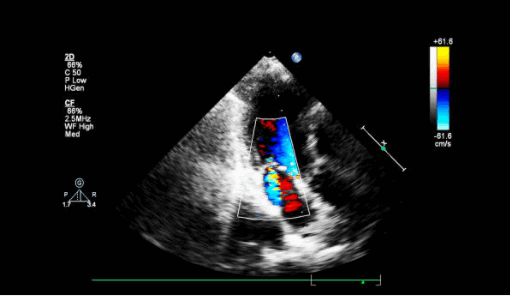

Острая митральная регургитация (молотящая створка МК) на эхокардиографии

Митральная регургитация (МР) может возникать как остро, так и хронически у пациентов с ИМ. Когда в дни после большого инфаркта миокарда возникает внезапная гипотензия и респираторный дистресс, одной из возможных причин может быть разрыв тела, кончика или хорд сосочковой мышцы, вызывающий острую тяжелую МР. Приводим алгоритм действия

- Поместите цветной допплеровский сектор на митральный клапан и левое предсердие. Посмотрите есть ли струя митральной регургитации (высокоскоростной или турбулентный пятнистый поток в систоле)? Во многих случаях он будет направлен эксцентрически либо к передней, либо к задней стенке левого предсердия. Как правило, молотящая створка МК направляет струю MР в сторону от самой поврежденной створки.

- Повторите двумерное (2D) изображение и цветное допплеровское сканирование митрального клапана в апикальном четырехкамерном и апикальном трехкамерном срезе. По техническим причинам низкое качество изображения нередко препятствует абсолютному определению того, есть ли молотящая створка МК, но есть эксцентрическая струя значимой МР или хордальная структура, колеблющаяся в левом предсердии проксимальнее митрального клапана, что повышает вероятность разрыва митрального аппарата.